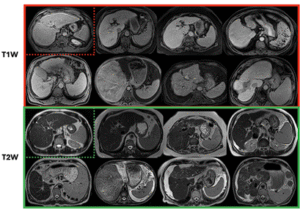

CirrMRI600+

628 abdominal MRI volumes (T1W: 310, T2W: 318) with physician masks for liver cirrhosis research; single-center, multivendor, multisequence.